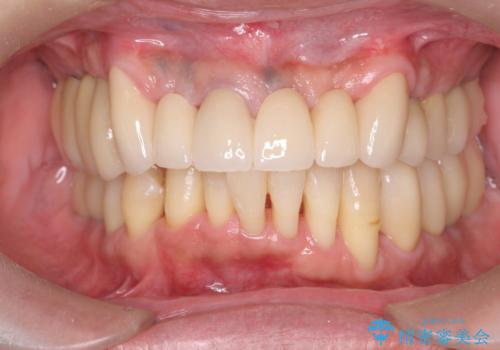

セラミック・インプラント治療を含む包括歯周病治療

できる限り口の中を綺麗にしたい。